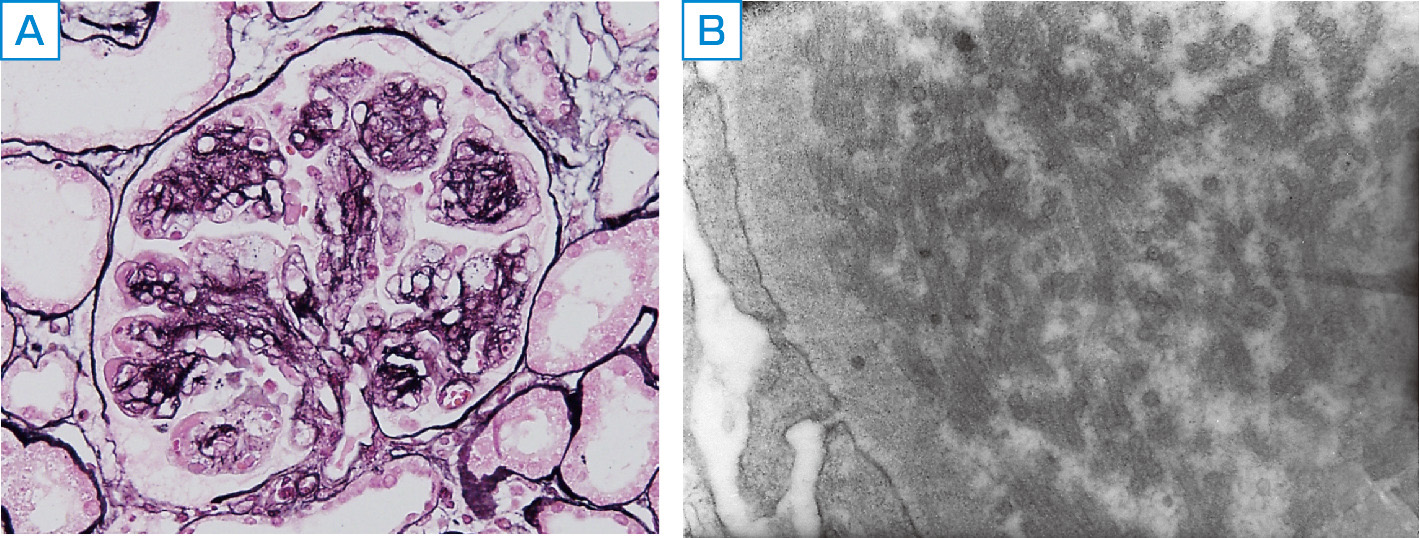

ⓔ図14-6-4 イムノタクトイド糸球体症の腎臓病理所見 A:膜性増殖性糸球体腎炎様病変 (PAS染色,×400). B:内皮下領域に認められる微小管状構造 (電子顕微鏡,×8000).